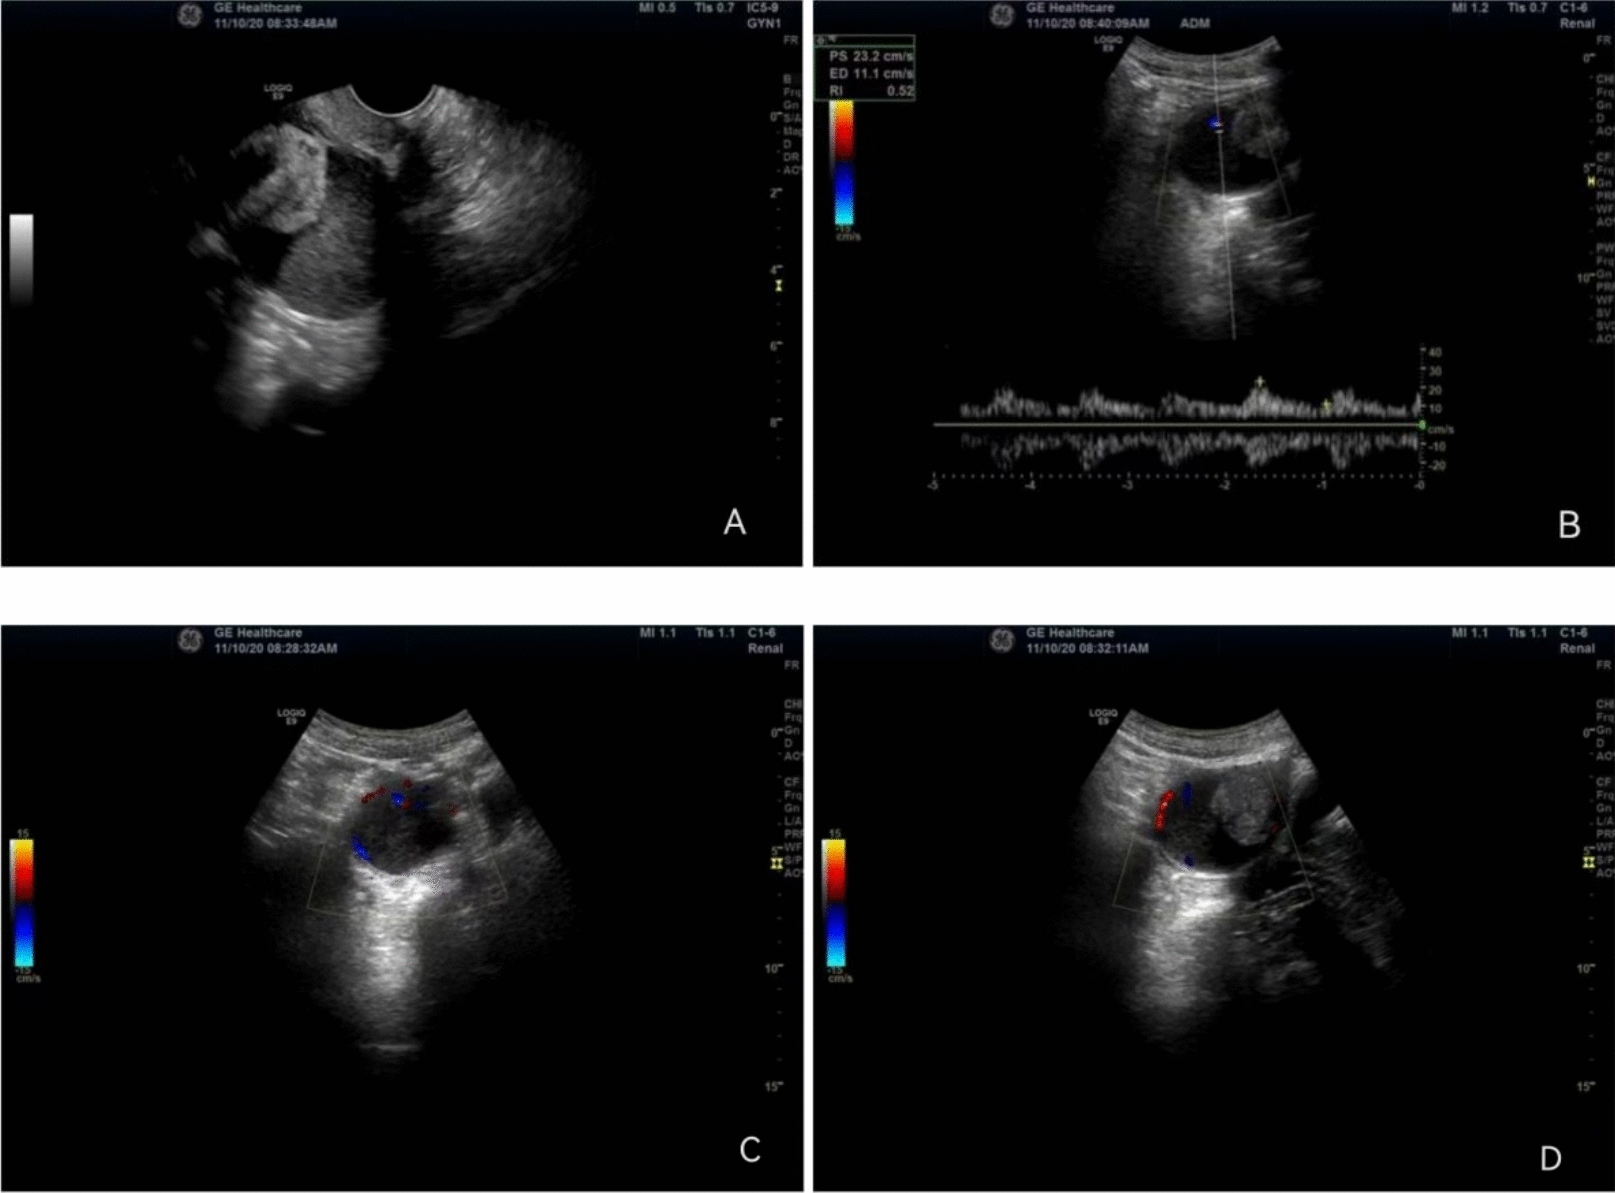

Case presentation: A 58-year-old married Chinese female patient had undergone annual check-ups at our hospital from 2007 to 2024, totaling 18 visits. During her initial examination in 2007, uterine fibroids were detected. She experienced natural menopause in 2010. By 2019, no significant changes were observed in the size or characteristics of the uterine fibroids. In 2020, follow-up examinations revealed an increase in the size of the fibroids, although the patient reported no significant subjective symptoms. A preliminary diagnosis of sarcomatous transformation of uterine myomas was made. Subsequently, the patient underwent surgical intervention at an alternative medical facility. Postoperative pathology confirmed the diagnosis of sarcomatous transformation of uterine fibroids. As of the time of writing, she has been attending regular follow-up appointments annually since then, with the most recent visit occurring in November 2024. Currently, the patient's overall health status remains stable, with no reported discomfort. Gynecological examinations and tumor markers (carbohydrate antigen 125 [CA125], carbohydrate antigen 199 [CA199], alpha-fetoprotein [AFP], and carcinoembryonic antigen [CEA]) are all within normal limits.